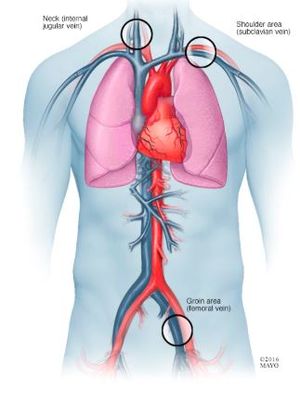

بعد أن يبدأ تأثير المهدئ، سيقوم الطبيب أو أخصائي آخر بتخدير منطقة صغيرة بالقرب من إحدى الأوردة على الأريبة، أو الرقبة أو الساعد. سيقوم الطبيب بإدخال إبرة إلى الوريد ووضع أنبوب (جراب) عبر الإبرة.

سيقوم الطبيب بإدخال القسطرة عبر الجراب وتوجيهه إلى العديد من الأماكن داخل القلب. ربما يقوم الطبيب بحقن صبغة في القسطرة، الأمر الذي يساعد فريق الرعاية في رؤية الأوعية الدموية والقلب باستخدام التصوير بالأشعة السينية. تحتوي القسطرة على أقطاب على الأطراف يمكن استخدامها لإرسال نبضات كهربائية إلى قلبك وتسجيل النشاط الكهربي لقلبك.